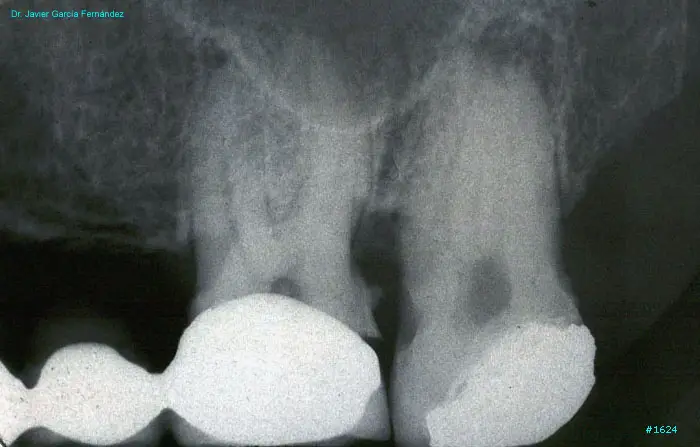

image 137